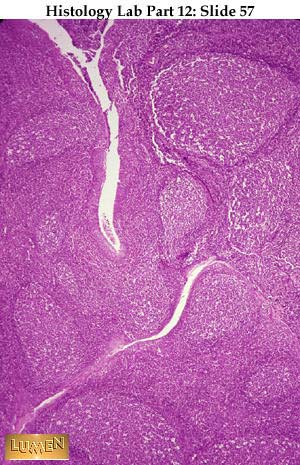

Slide 57

H&E stain of tonsil with stratified squamous epithelium lining the lumen of crypts. Often such epithelium is all but hidden by lymphocytes wandering through it. Note lymphatic nodules with germinal centers, indicating active production of plasma cells from B-lymphocytes.